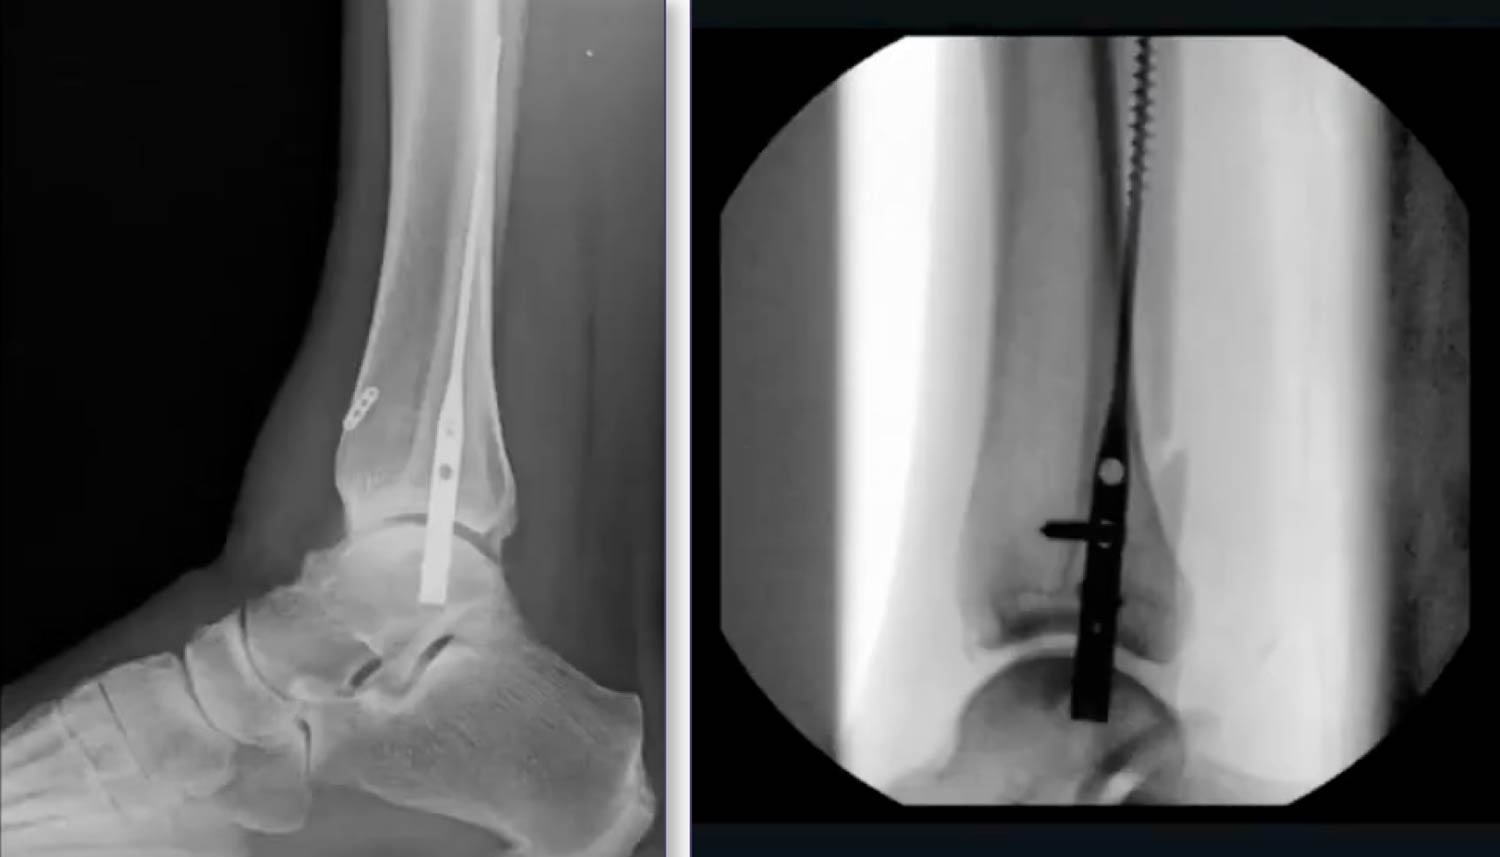

Surgical Technique and Reduction Strategies

A common misconception is that the nail itself achieves the reduction. Experts emphasize that the surgeon must reduce the fracture before or during nail insertion.

Percutaneous Reduction Tips

- Manual Restoration: Use thumbs to push the distal fragment anteriorly and pull it out to length by manipulating the peroneals.

- Clamping: Utilize a large, pointed reduction clamp from the medial malleolus to the distal fibula to close the medial clear space. A second percutaneous clamp can be used anterior-to-posterior (A-to-P) to close the fracture site.

- Maintaining Reduction: It is recommended to keep the reduction clamp in place while inserting the nail to prevent the hardware from displacing the fracture or causing shortening.

Radiographic vs. Functional Outcomes

The study utilized the McLennan and Ungersma guidelines to qualify reductions as “good,” “fair,” or “poor.”

- Reduction Accuracy: 97% of cases were reduced to length; 100% achieved closure of the medial clear space.

- Acceptable Displacement: Approximately 9% of cases showed “fair” reduction, often involving a 1–2 mm posterior displacement. This is frequently due to the syndesmotic screw/button passing through the fracture site.